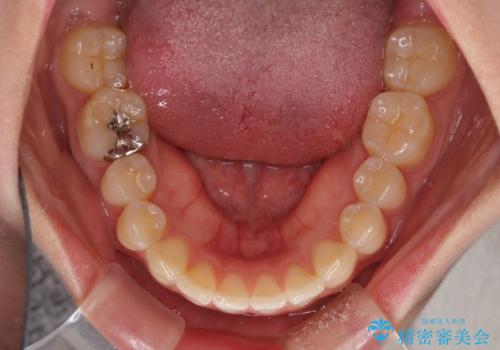

気になる前歯を治したい インビザライン矯正とオールセラミッククラウン

- 変色した前歯と突出した口元を気にして来院された患者様です。

口元の突出感はインビザラインにより歯列を整え、その後に、前歯をオーダーメイドタイプのオールセラミッククラウンにて補綴治療することとしました。

長時間のマウスピース装着と、患者様自身でのゴムかけに協力いただき、口元の突出感をしっかりと改善することができました。